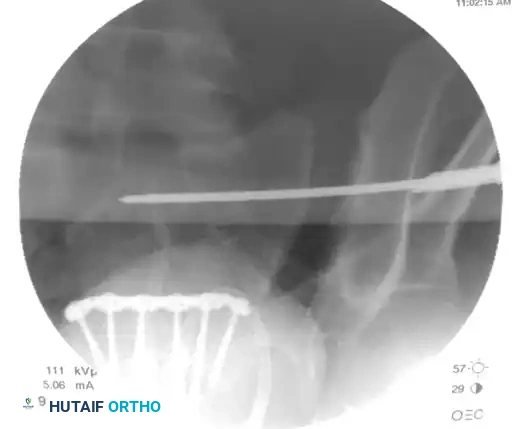

On the lateral fluoroscopic view, place the tip of the guide on the exact predetermined starting spot. Once positioned correctly, impact the guide firmly into the iliac cortex using a mallet. This creates a stable docking point and prevents the guide from skiving along the curved iliac wing.

Image